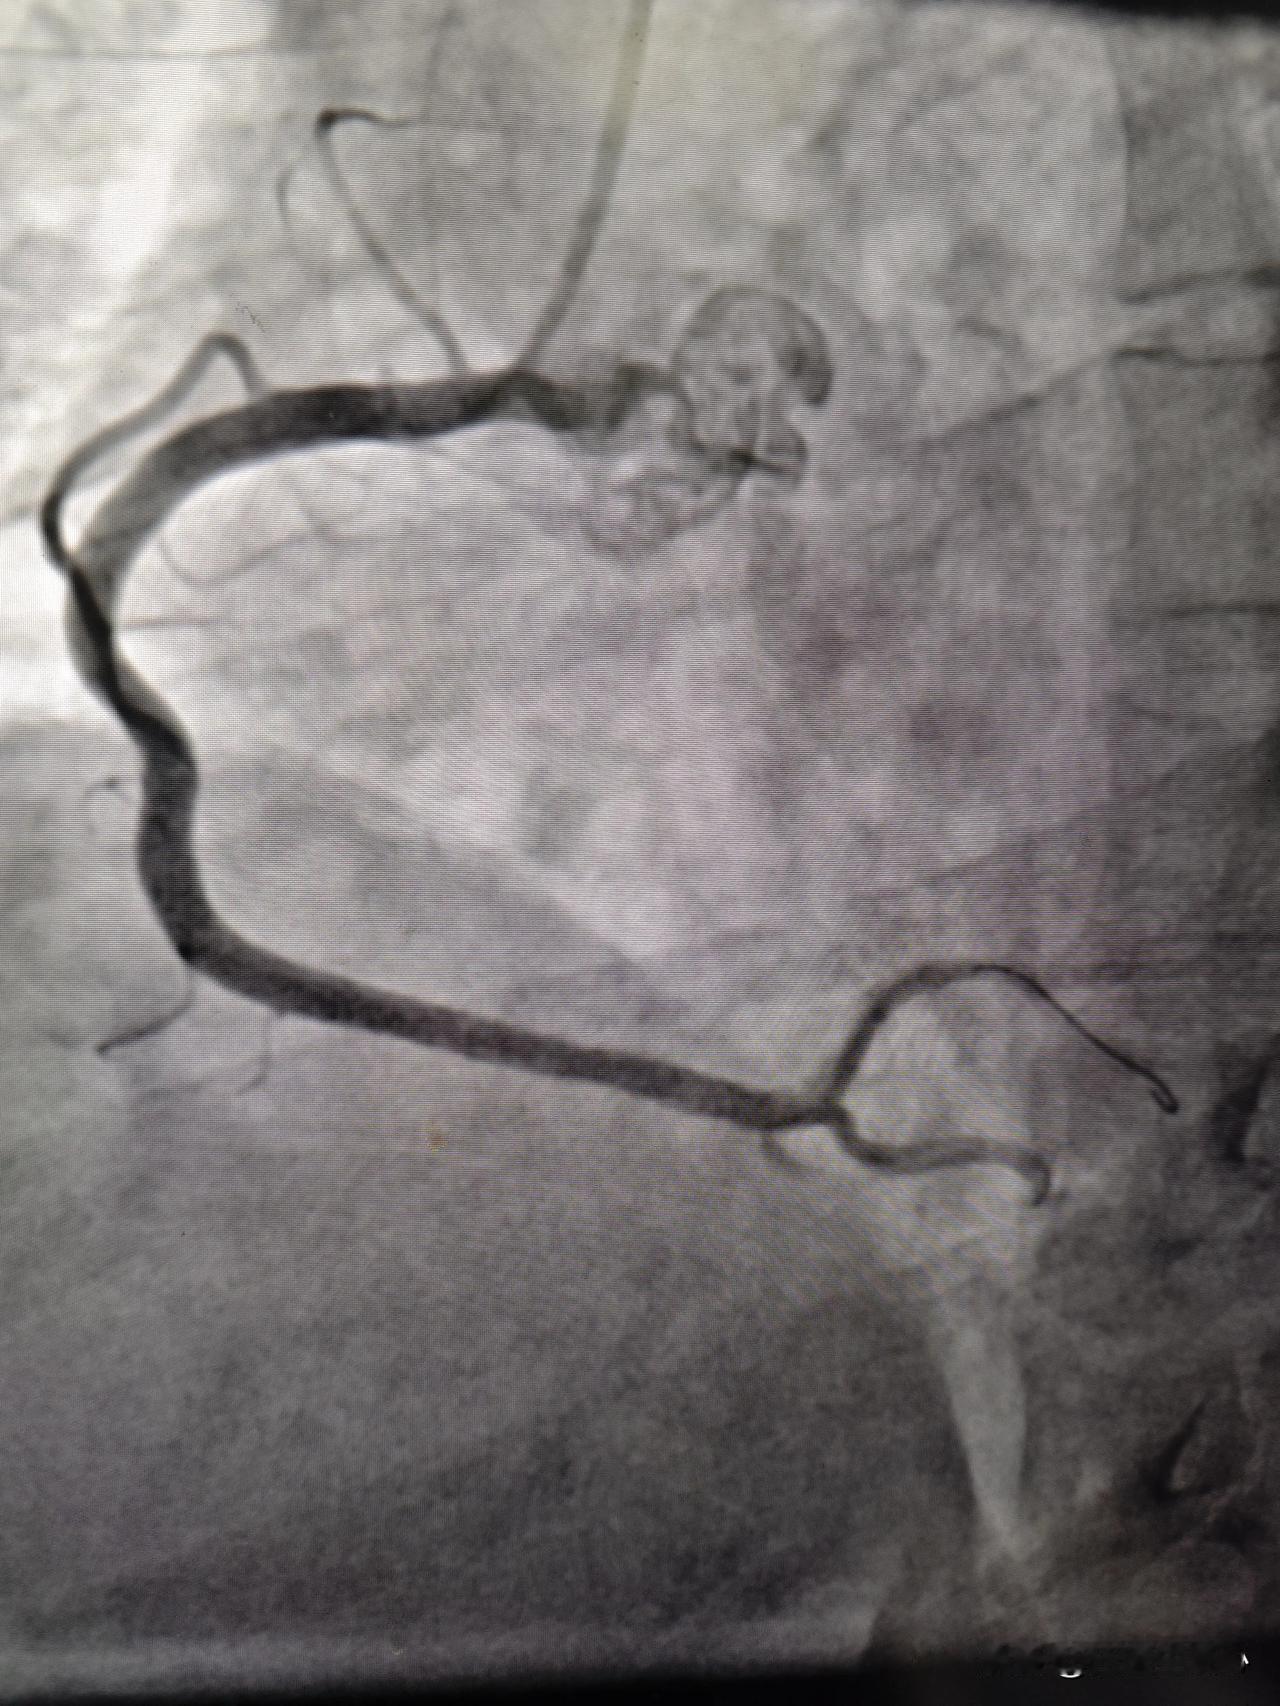

39岁小伙突发剧烈胸痛,又是心梗!昨天下午刚做完一台急诊手术,晚上又来了一台。39岁的小伙子胸痛一个小时送到医院,一做心电图,发现是急性下壁ST段抬高型心肌梗死。 剧烈的胸痛让小伙子丧失了理智,大喊大叫,捶着自己的胸口,不得已注射了吗啡和镇静药物止痛。 赶紧绿色通道送往手术室,造影发现冠状动脉是右优势型,也就是说右冠状动脉为心脏提供了更多的供血。这个巨大的右冠状动脉完全闭塞,缺血范围太广泛了,怪不得症状这么严重,心电图上ST段抬的也非常高。立马进导丝通过闭塞段到远端的血管,用球囊扩张以后,发现这个地方有一个严重的狭窄,在动脉硬化斑块的基础上,斑块破裂以后,诱发局部长血栓造成的血管闭塞。植入一枚支架后,血流恢复通畅。 再次劝告这位老哥不要再抽烟了,回答说能不能每天少抽一点,以前每天两包,现在每天抽1包行不行?我说小伙子,你都疼成这样了,还不忘记抽烟,看来是真爱。 从危险因素阶段,比如高血压、糖尿病、血脂高发展为明确的动脉硬化的斑块,再到冠状动脉严重的狭窄,是一个漫长的过程,起码是5~10年。这期间如果能够很好地控制这些危险因素,就能避免血管病变的加重。在叠加抽烟、生活方式不健康、熬夜、饮食油腻这些危险因素,这个进程会大大加快。 所以为了我们的心血管健康,除了控制好危险因素,比如高血压、高血糖、高血脂,另外还要注意生活方式的健康。